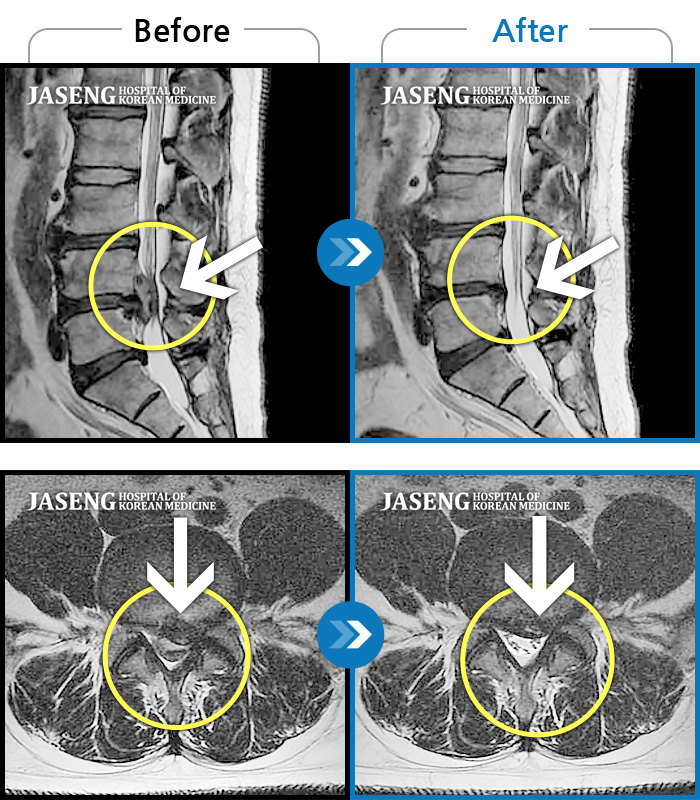

허리디스크

수원 · 김태성 원장

우측 허리 통증과 우측 다리 방사통으로 활동하기 힘든 상태

촬영시기

2021.02.03 ~ 2021.07.09

2022.03.25